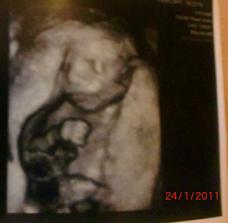

24.1.2011 - dozvěděli jsme se,že čekáme druhýho chlapečka - Matyáška

4.2.2011 - Velký utz,potvrzen chlapeček,vše je v pořádku,jen je Matýsek moc dole a tak byl problém ho změřit..